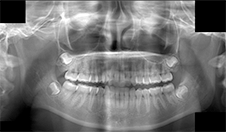

図❷ 右下大臼歯部に骨の異常所見はあきらかではなかった

画像所見:パノラマX線写真とCT画像で顎骨ならびに歯に異常所見は認めなかった(図❷❸)。